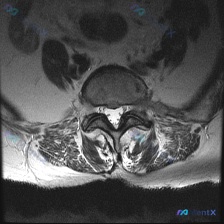

腰椎MRI轴位读片:这个椎间盘病变背后隐藏了哪些问题?

看到这张腰椎MRI轴位的椎间盘病例,整理了完整的读片和分析思路,和大家一起讨论。

这是腰椎MRI T2序列的轴位影像,层面位于下腰椎水平,可清晰显示椎体、椎间盘、椎管及周围软组织结构:

- 核心异常信号:椎间盘髓核信号明显减低,呈中等偏低信号,不符合正常髓核的高信号表现,提示存在明显椎间盘退变

- 椎间盘形态:椎间盘后缘形态不光滑,存在向后方的弥漫性膨出,已经累及双侧侧隐窝和神经根通道

- 椎管与硬膜囊:硬膜囊前后径明显受压变小,形态变成「三叶草」/哑铃状,提示明显椎管狭窄

- 其他结构改变:双侧小关节突关节缘增生肥大、边缘锐利;后方黄韧带明显增厚,占据椎管空间进一步加重狭窄;椎旁竖棘肌信号对称,未见明显异常;硬膜囊内可见点状低信号的马尾神经束

第一眼看到这张片子,最突出的改变就是多结构共同参与的退行性改变:椎间盘退变+韧带肥厚+骨质增生,共同导致了椎管狭窄,这是最直观的第一印象。